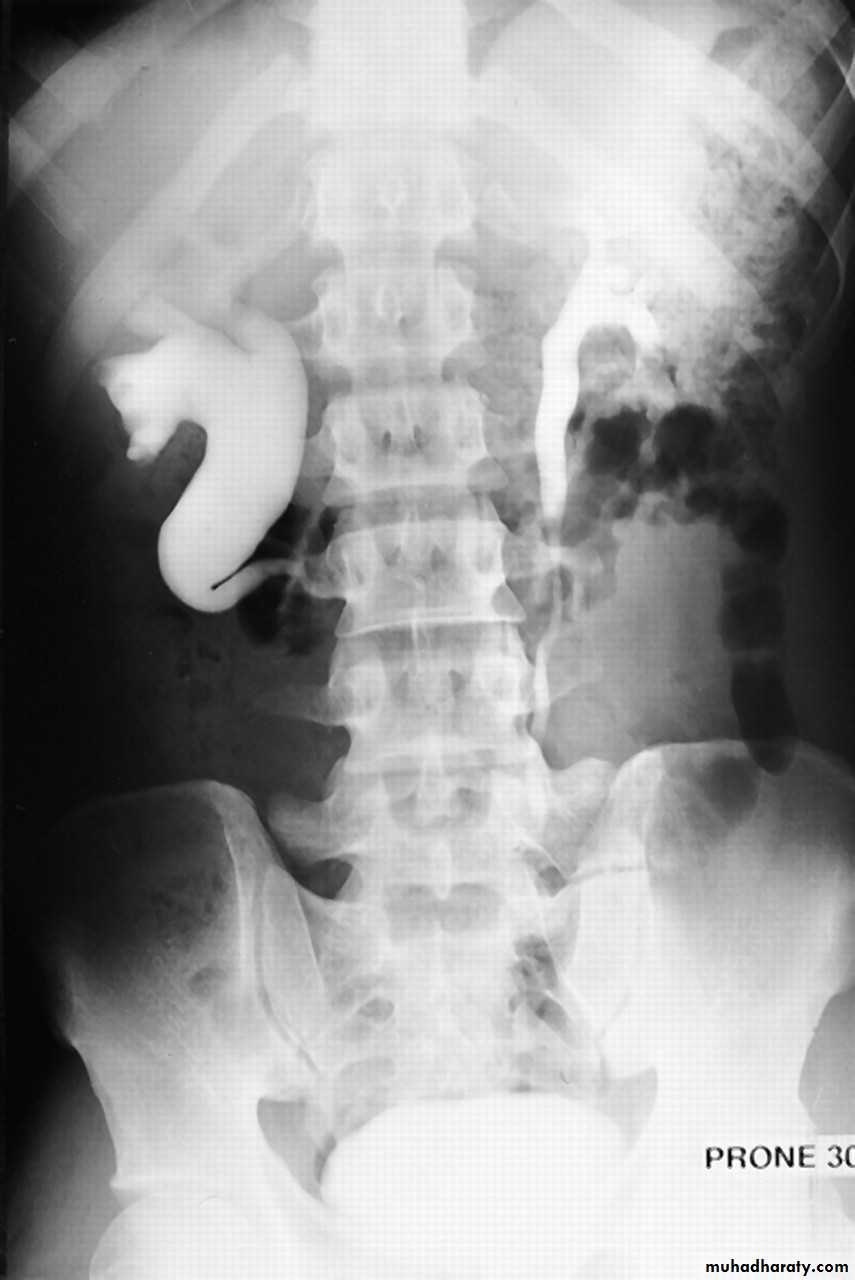

IVU shows

1. The kidneys at low position .

2.Close to the spine with long axis parallel to the spine .

3. Malrotation manifested by medially directed calyces.

4- The renal pelvis and ureters are anterior and lateral in position .